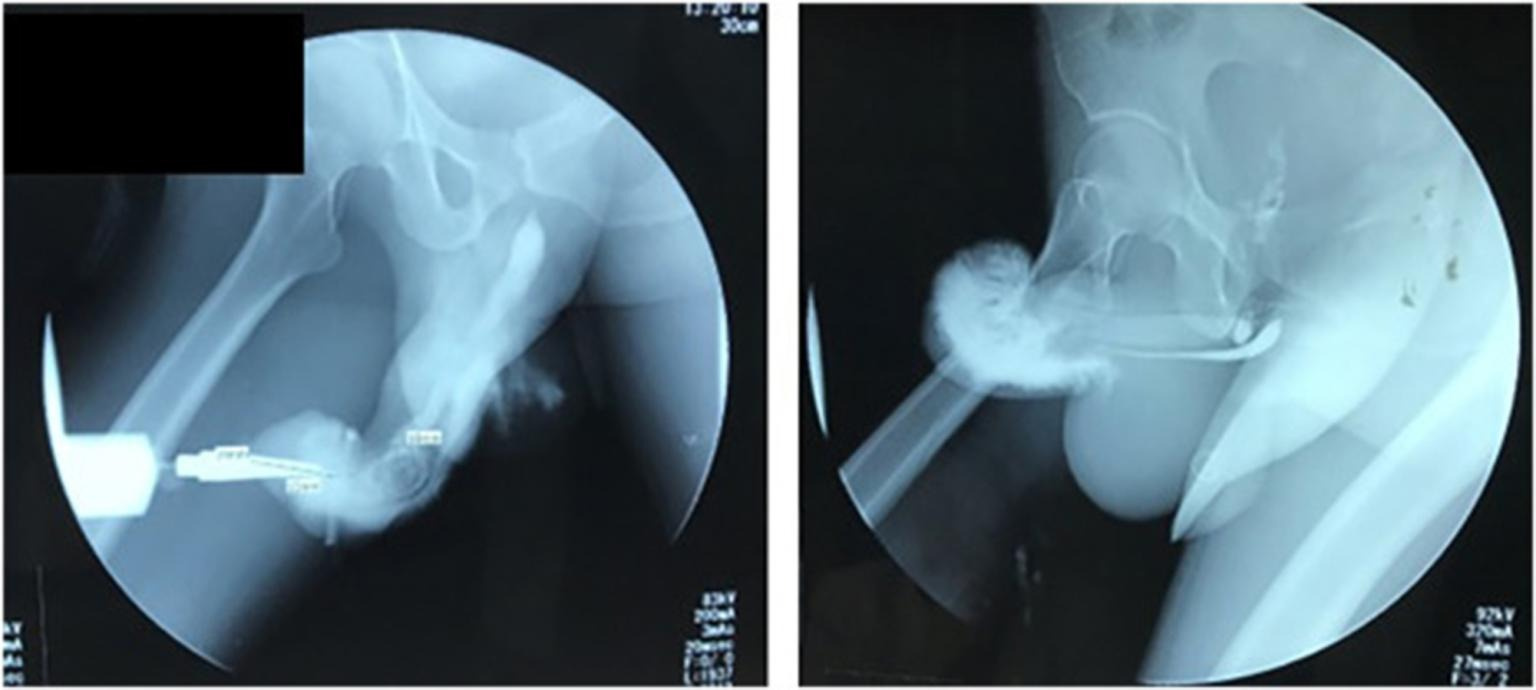

Мужчине из Индонезии пришлось перенести экстренную операцию после того, как он сломал пенис из-за рискованной позы во время секса. Исследование случившегося опубликовали в журнале Urology Case Reports. Несчастный случай произошел, когда неназванный 37-летний мужчина решил попробовать со своей возлюбленной положение «обратной наездницы» (“reverse cowgirl”): женщина находилась сверху и спиной к своему мужчине.